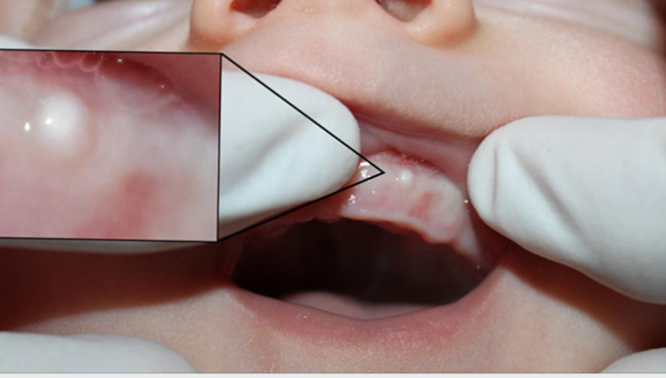

epstein’s pearls

small, white cysts along MEDIAN PALATAL raphe

bohn’s nodule

small, painless cysts located along the alveolar ridges, common in newborn

neonatal teeth

teeth that are present with first 30 days after birth, often being primary incisors that appear earlier than usual.

natal teeth

teeth that are present AT BIRTH, typically primary incisors, which can cause feeding difficulties or dental issues.